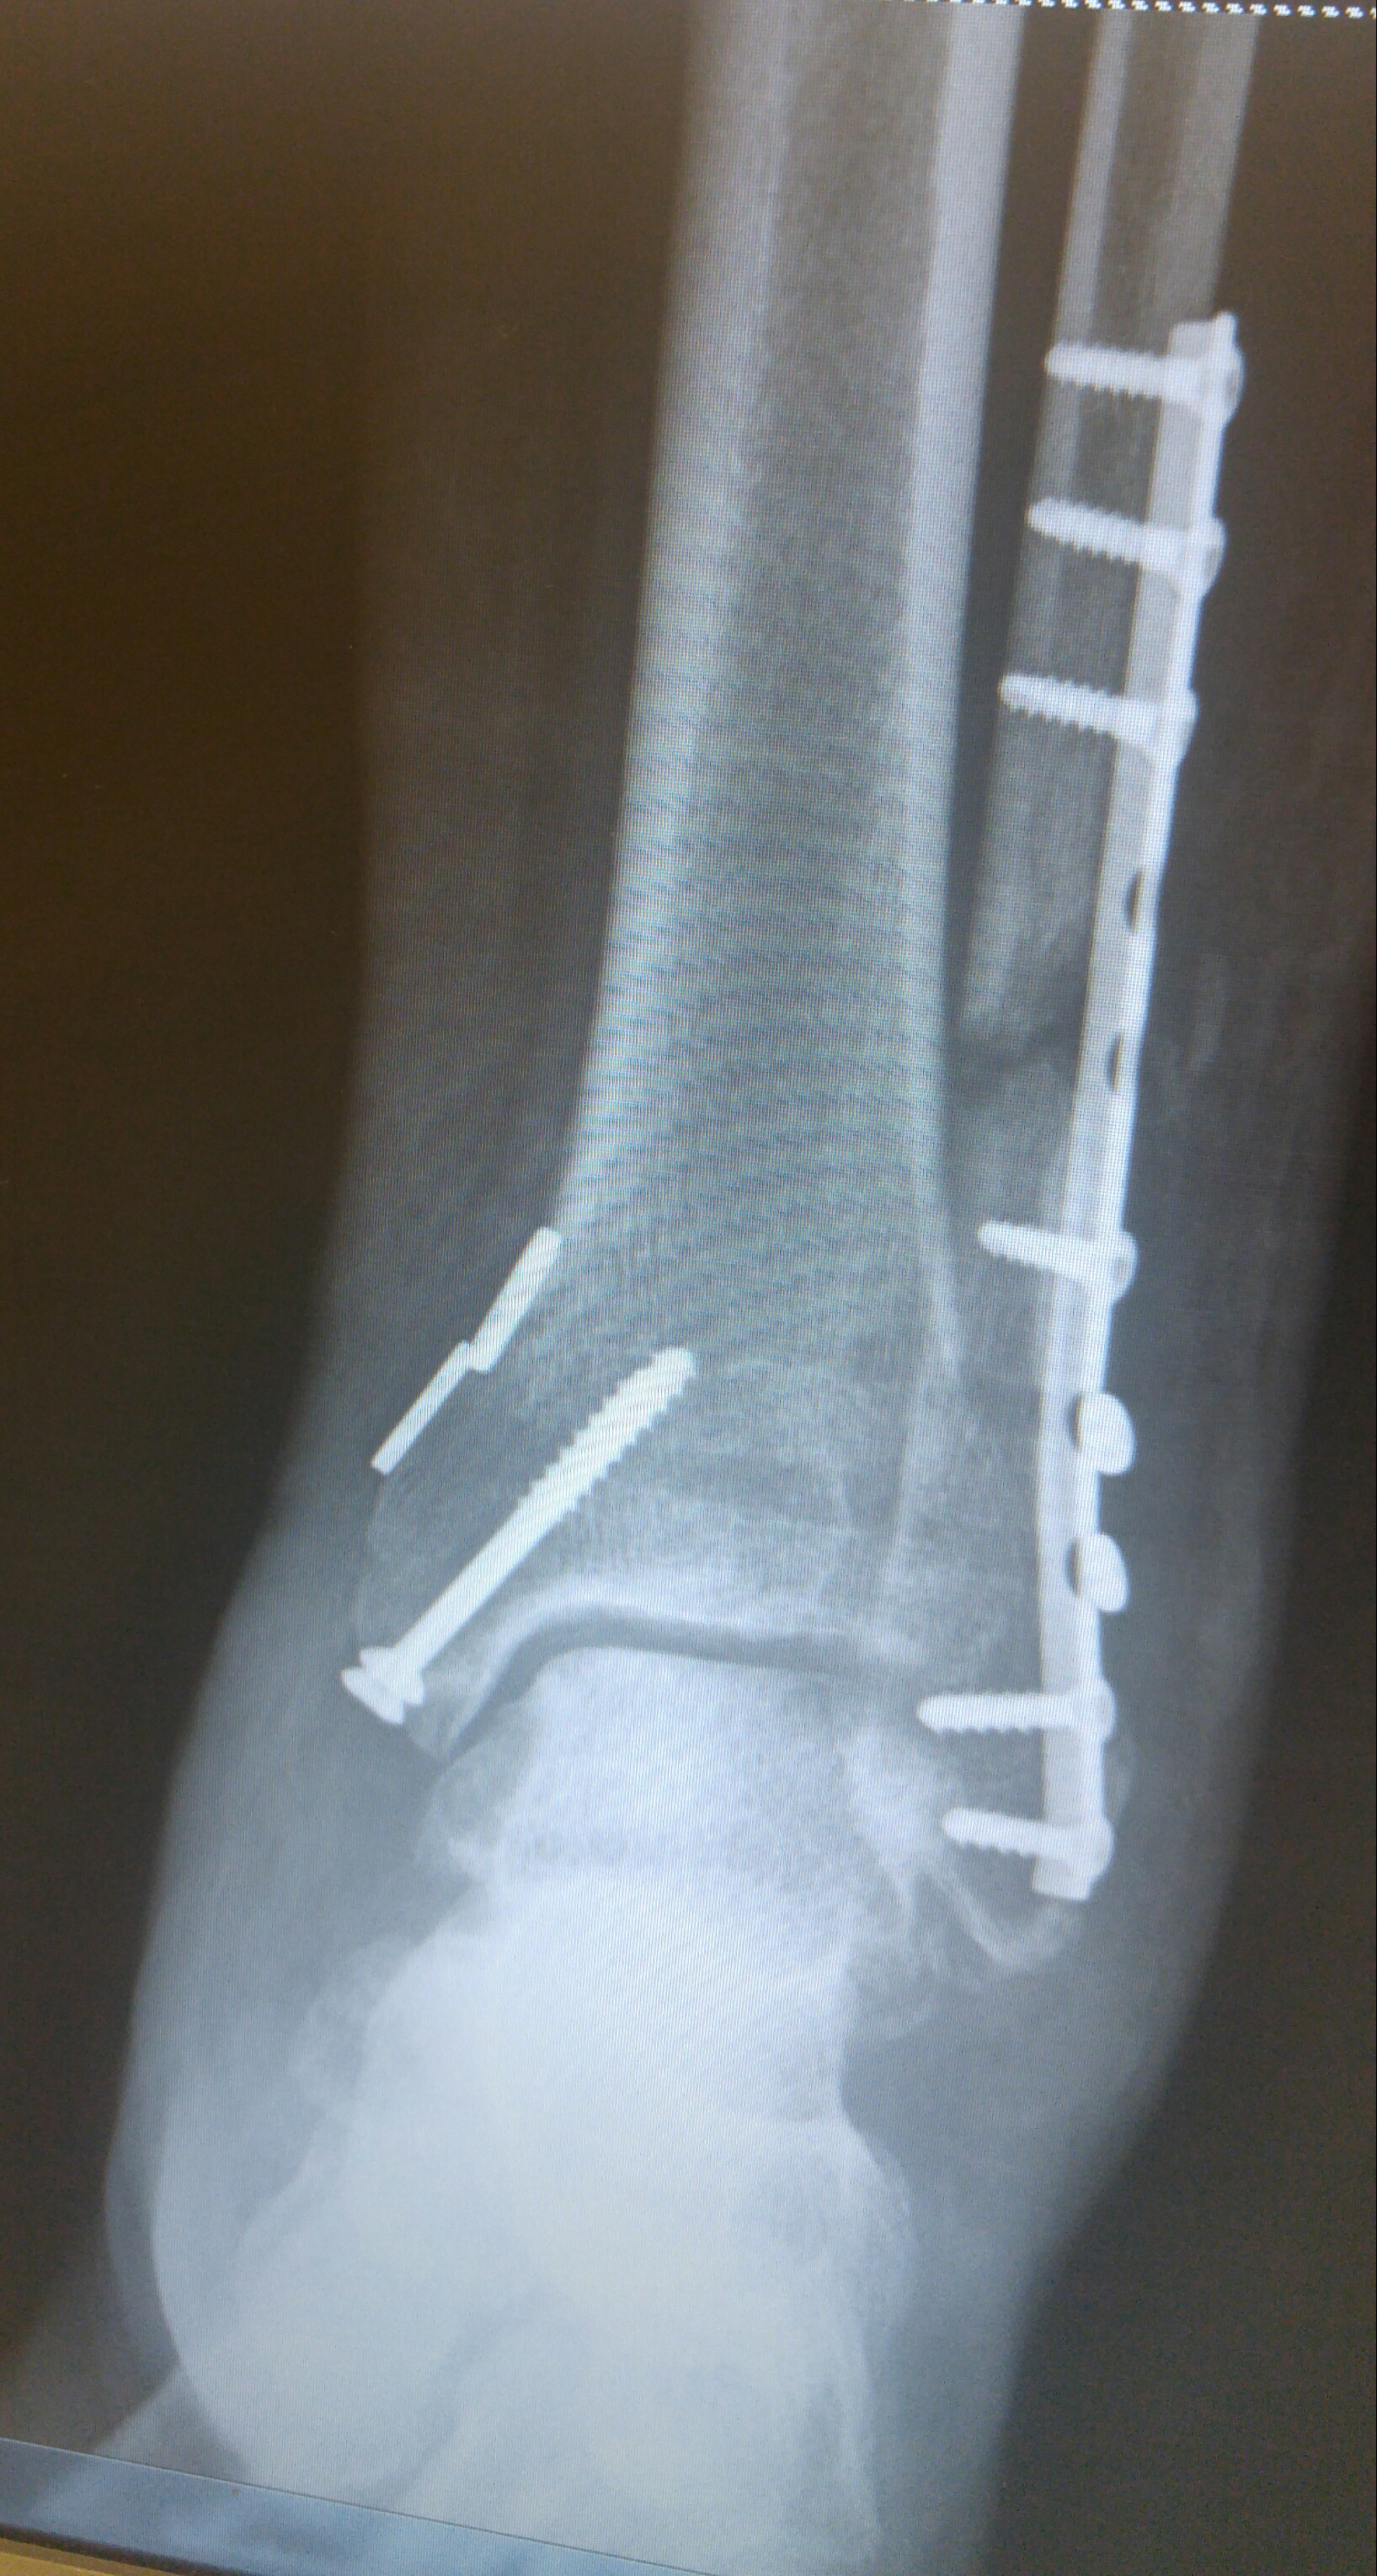

Broke my able and tore the ligament that hold the fibula and tibia in place. Did it on May 13 and here are my x-rays that were taken yesterday. Be as compliant as you can so you don't have to join the hardware club.

Due to the remaining gap in the fibula, it will be at least another 2 weeks before I can start putting any weight on it.

Thankfully, no. Just lots of screws, a plate and some heavy duty thread to secure the two bones in place until the ligaments heal. If you zoom in and look close at the bottom of my tibia and fibula, you will see two light grey horizontal lines. Those are the tunnels drilled and ran the sutures through to tie the two bones together. This technique is supposed to allow for more natural range of motion down the road.

I shared the xrays just to encourage you to be compliant with the doc's instructions. If you do, your chances of avoiding surgery will increase. I had no choice about surgery. Hopefully you will be able to avoid the surgery.